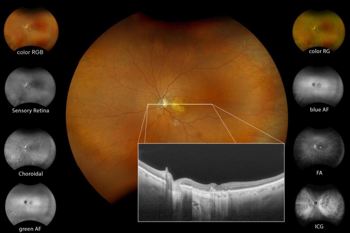

Silverstone RGB, Optos’ pathology reference guide

Combining 200° single shot true-to-life colour imaging with advanced swept-source OCT, the Silverstone RGB delivers nine imaging modalities in a single device, enabling clinicians to capture, visualise and analyse pathology across every layer of the retina. The nine modalities include optomap colour RGB for true-to-life retinal colour imaging; optomap colour RG as the proven clinical standard, supported by more than 3,000 peer-reviewed studies; optomap fluorescein angiography for vascular evaluation and disease detection; optomap indocyanine green angiography for enhanced choroidal and vascular imaging; optomap sensory red-free for highlighting nerve fibre and vascular structures; optomap choroidal imaging for deep tissue visualisation; optomap green autofluorescence for identifying RPE changes and metabolic activity; optomap blue autofluorescence for visualising subtle retinal pathology; and swept-source OCT for high-resolution, navigable imaging anywhere in the retina.

Optomap Recognising Pathology is a searchable reference resource to support clinical decision-making and to assist healthcare professionals identify pathology in optomap retinal images and OCT scans. All case images are from the latest ultra-widefield optomap device technology with results available by pathology and/or optomap image modality. For more visit: https://www.optos.com/recognizing-pathology/.